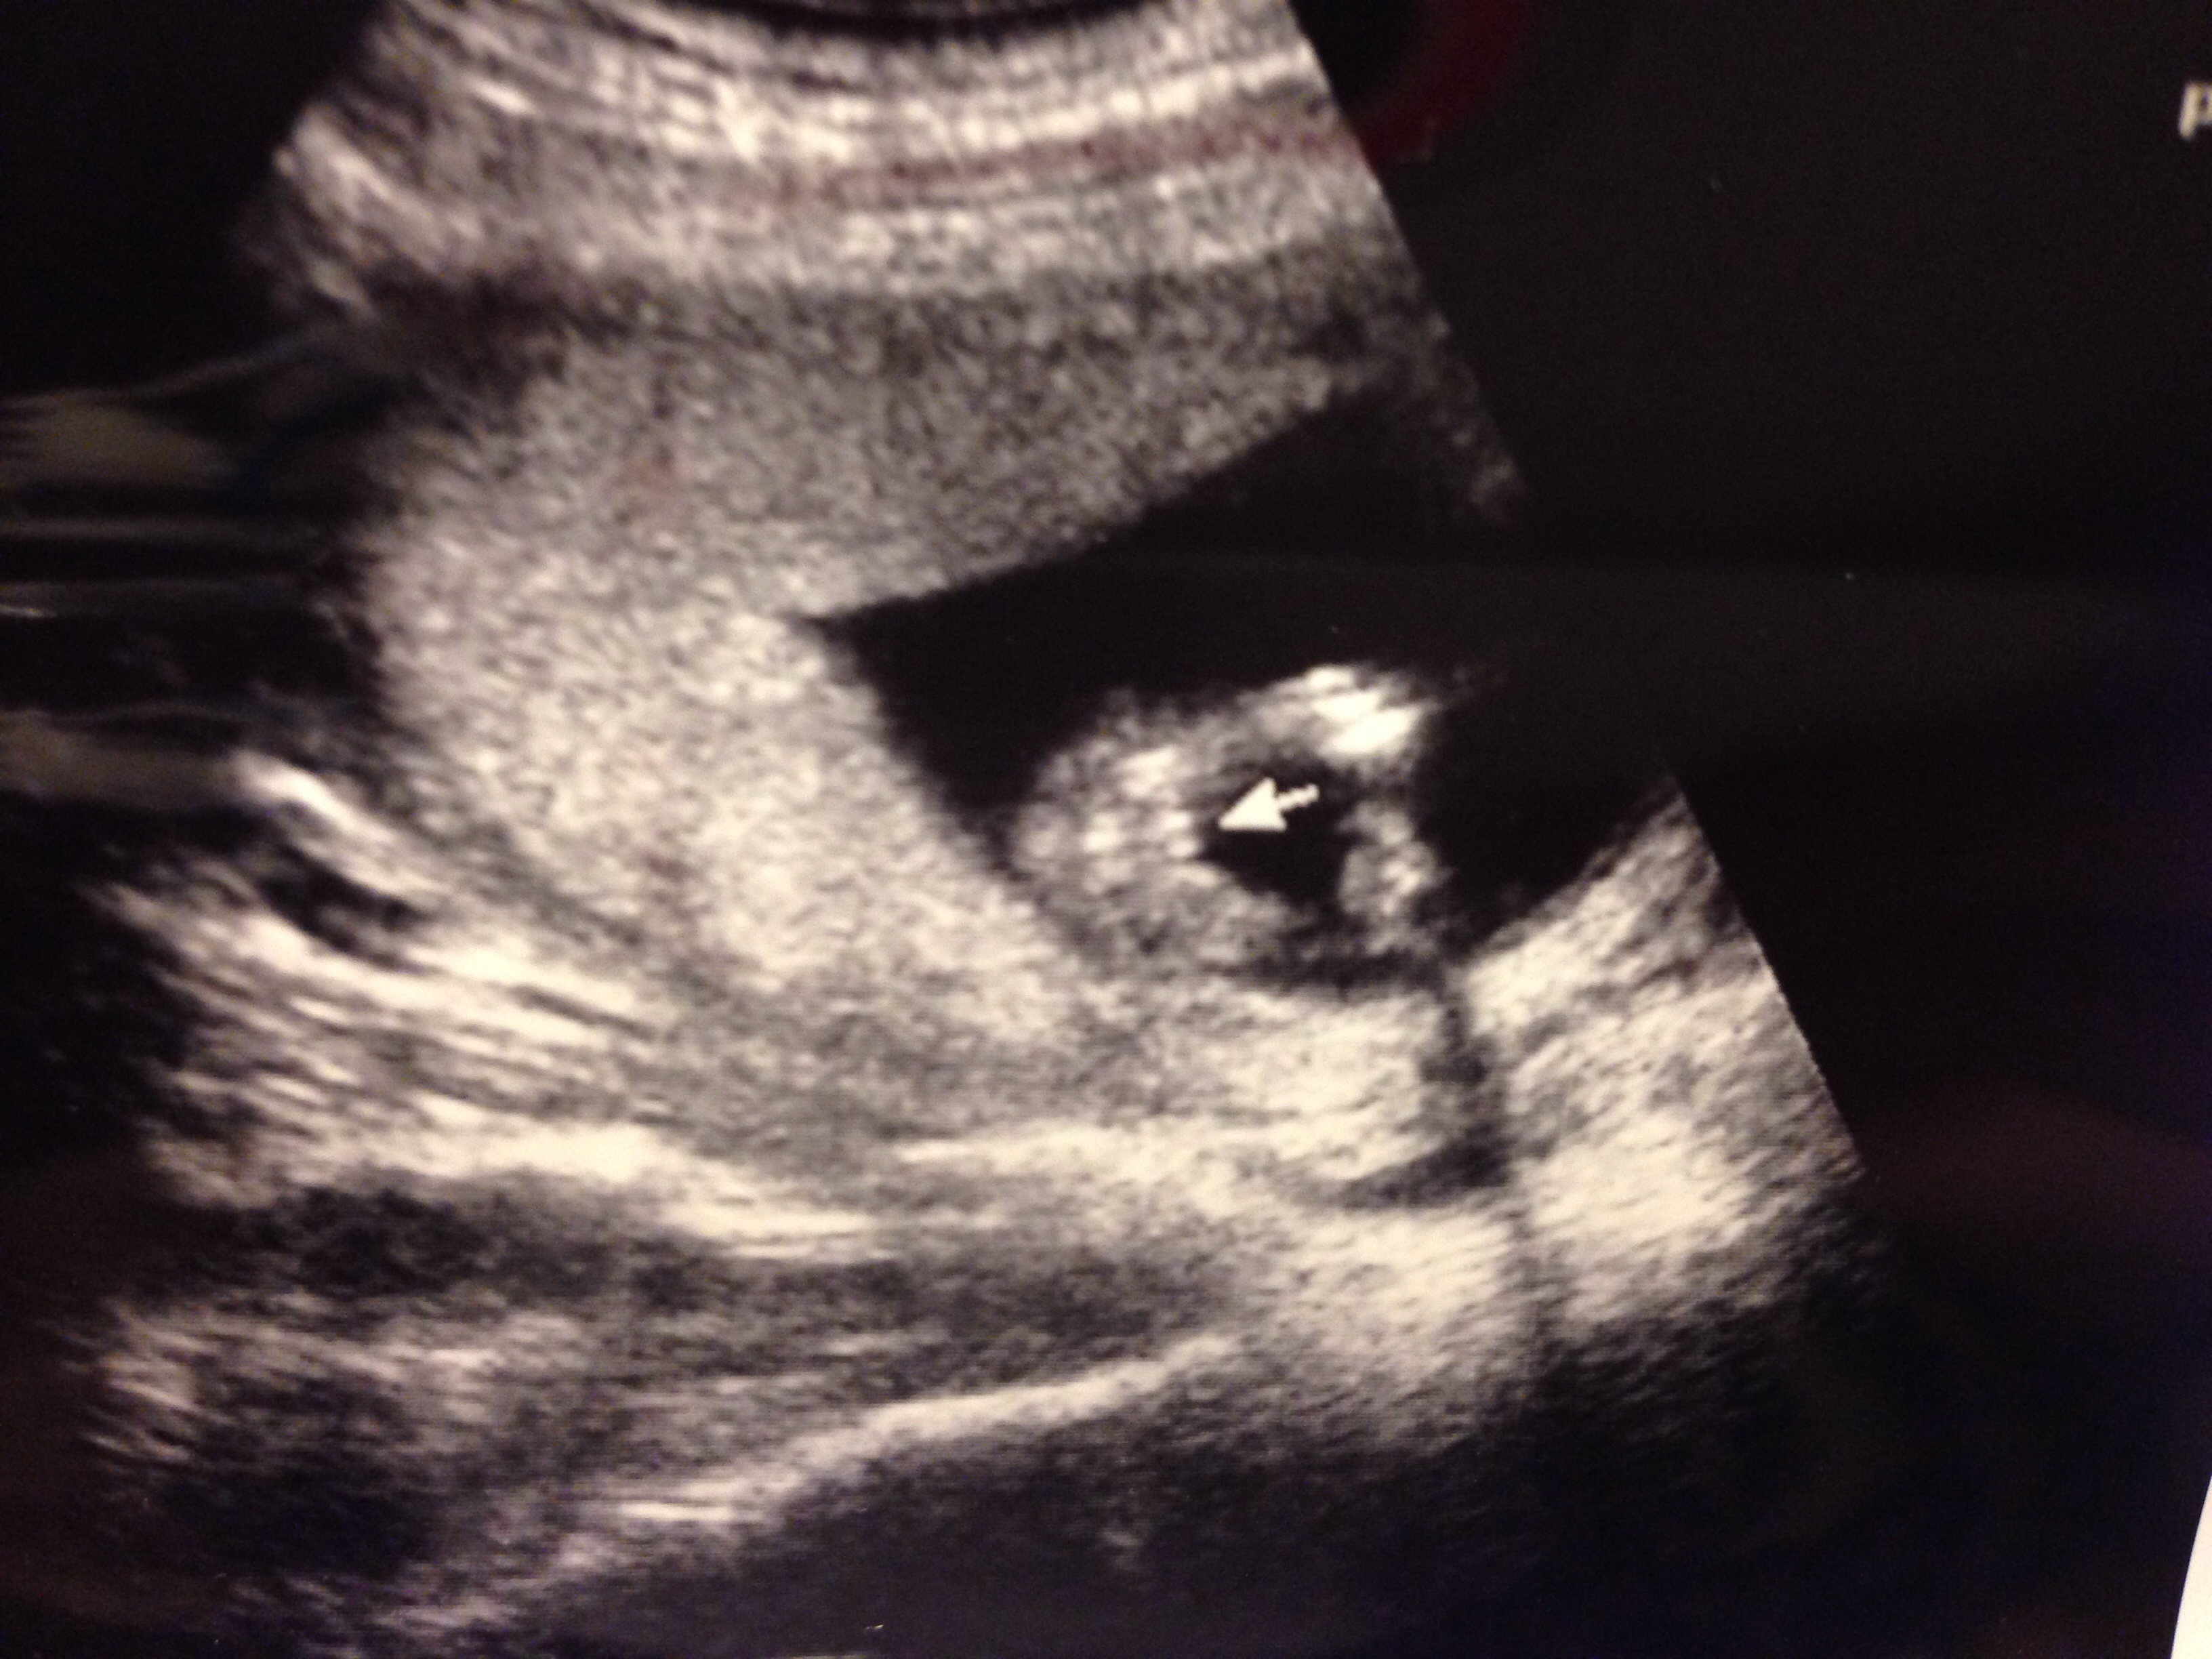

Hello everyone! I'm pregnant with our third and last child and was wondering if you could help me with my scan?

The tech told me her thoughts but it would be nice to get a second opinion!

Thank you for your time! Attachment 15043Attachment 15042Attachment 15043Attachment 15042